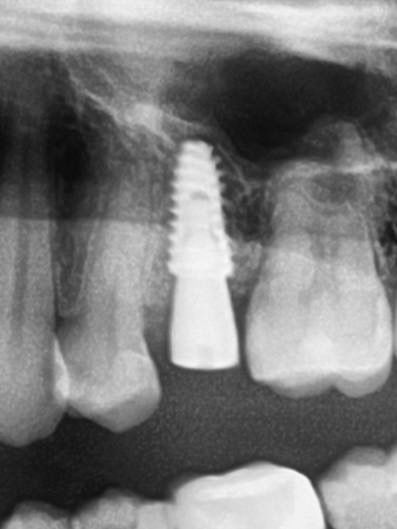

Установка импланта